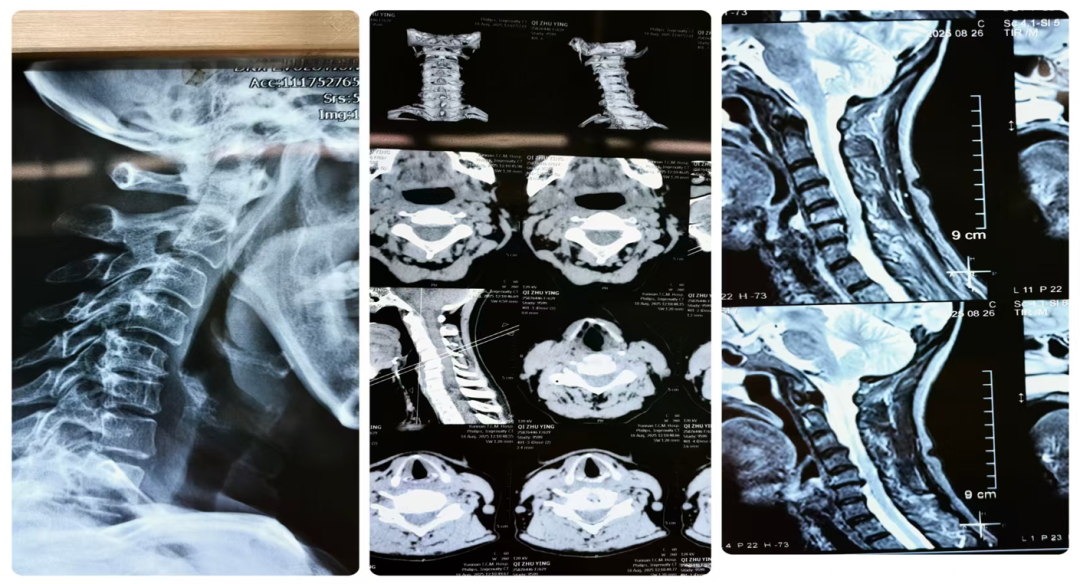

患者戚女士,62岁,长期罹患颈椎病,1月前颈肩背部疼痛加剧,抬头、低头时疼痛加重,经院外多方就诊治疗无效,后来到云南省中医医院疼痛科就诊收治入院。经过全面检查,诊断为:颈椎滑脱伴椎管狭窄(颈4/5)。颈椎锥体滑脱,患者必须尽早进行手术固定,否则有可能出现因刺激脊髓后摔倒至颈椎全脱位继发瘫痪甚至危及生命安全等风险。

陈建军主任组织多学科会诊,会诊专家同意诊断意见,并建议患者早期进行前路减压融合固定术。在主管医生与患者及家属全面深入沟通取得同意后,团队反复推敲最终制定了详尽缜密的手术方案,经过充分准备于2025年9月3日上午在麻醉科全面支持配合下行术中神经电生理监测,陈建军主任团队在内镜辅助下成功切除了增生的骨赘及后纵韧带,充分减压后成功植入‘零切迹’内固定装置,成功实施手术。